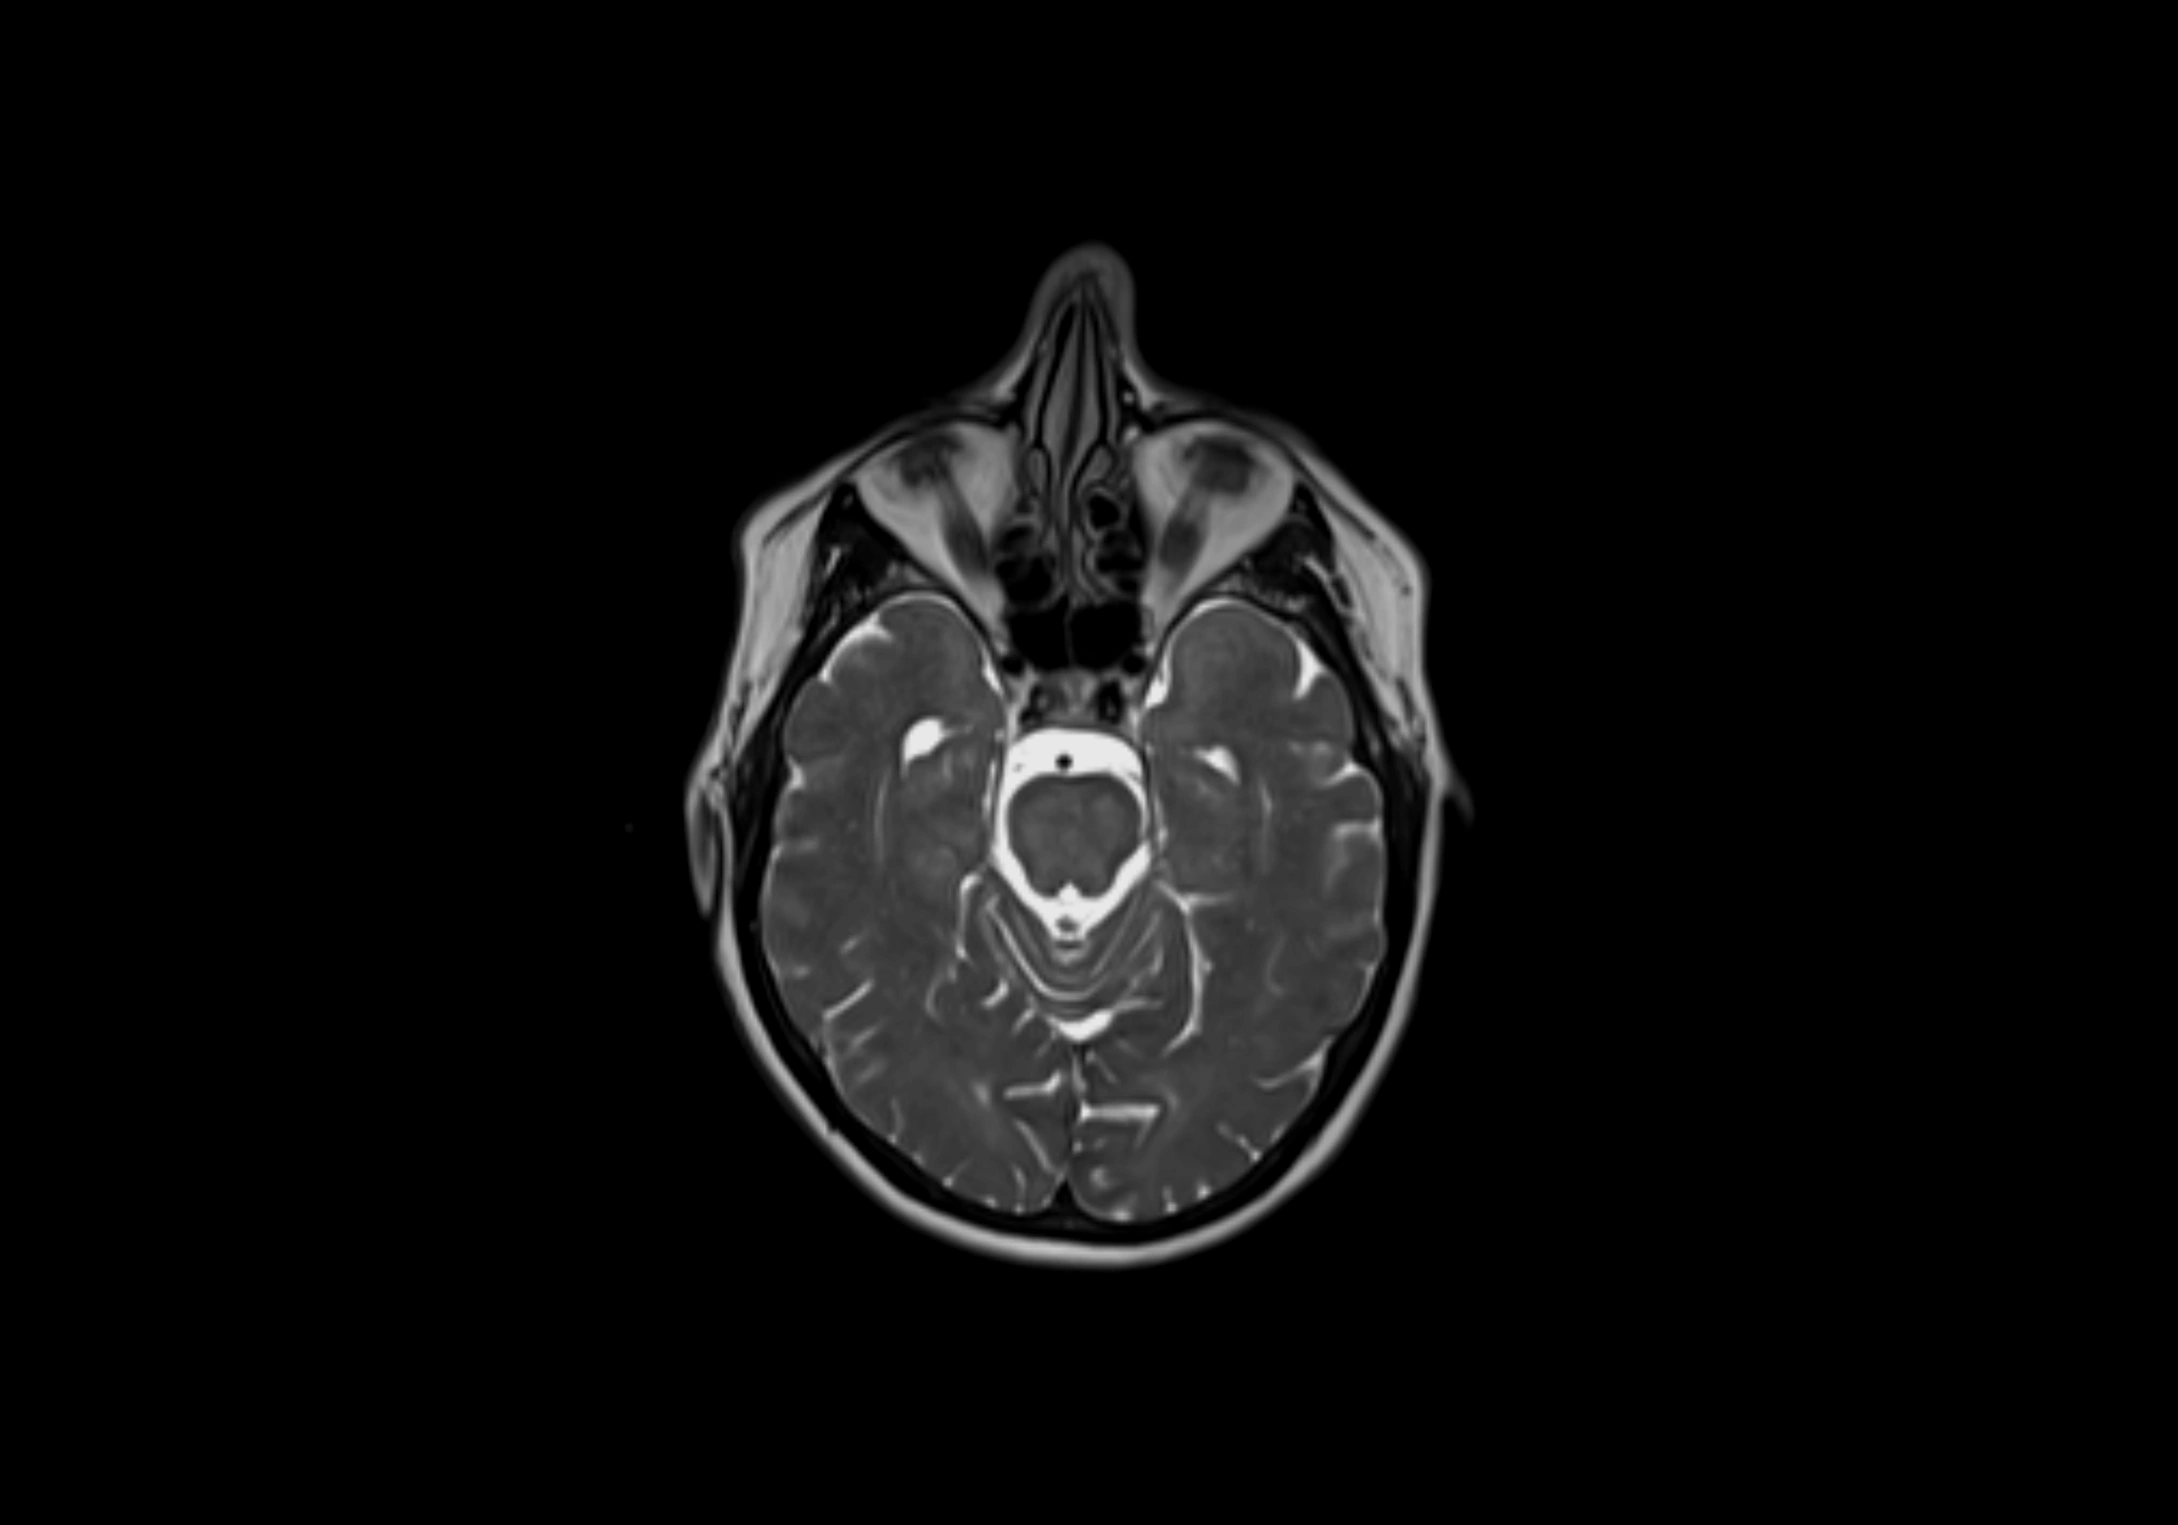

MRI Appearance

T2-weighted images:

• Nodes show intermediate signal, with surrounding fat bright

• Useful for detecting edema, inflammation, or infiltration

• Fatty hilum may appear slightly hyperintense relative to cortex

MRI images

image